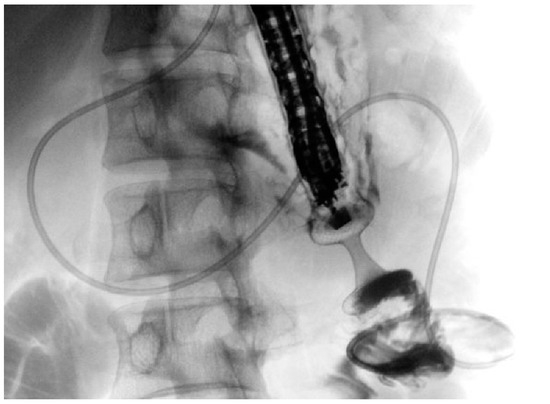

Historically, the treatment options for GOO have included surgical gastroenterostomy (S-GE) and enteral stenting (ES), which involves placing a metal stent through the stenosis [52]. While S-GE is highly effective, it is a surgical intervention associated with a notable risk of morbidity due to surgical complications and is often not feasible for patients unfit for surgery, such as those with advanced oncological disease. ES, on the other hand, is a minimally invasive procedure with a lower risk of AEs and good short-term efficacy [53]. However, it is frequently associated with stent obstruction, necessitating reintervention [54,55]. In this context, EUS-guided gastroenterostomy (EUS-GE) has emerged as a minimally invasive endoscopic alternative to S-GE for managing GOO. Like S-GE, EUS-GE involves creating a gastro-jejunal anastomosis, approximately 20 mm in size, by placing a fully covered dumbbell-shaped Lumen-Apposing Metal Stent (LAMS) under EUS guidance downstream of the obstruction (Figure 3) [13,56,57].